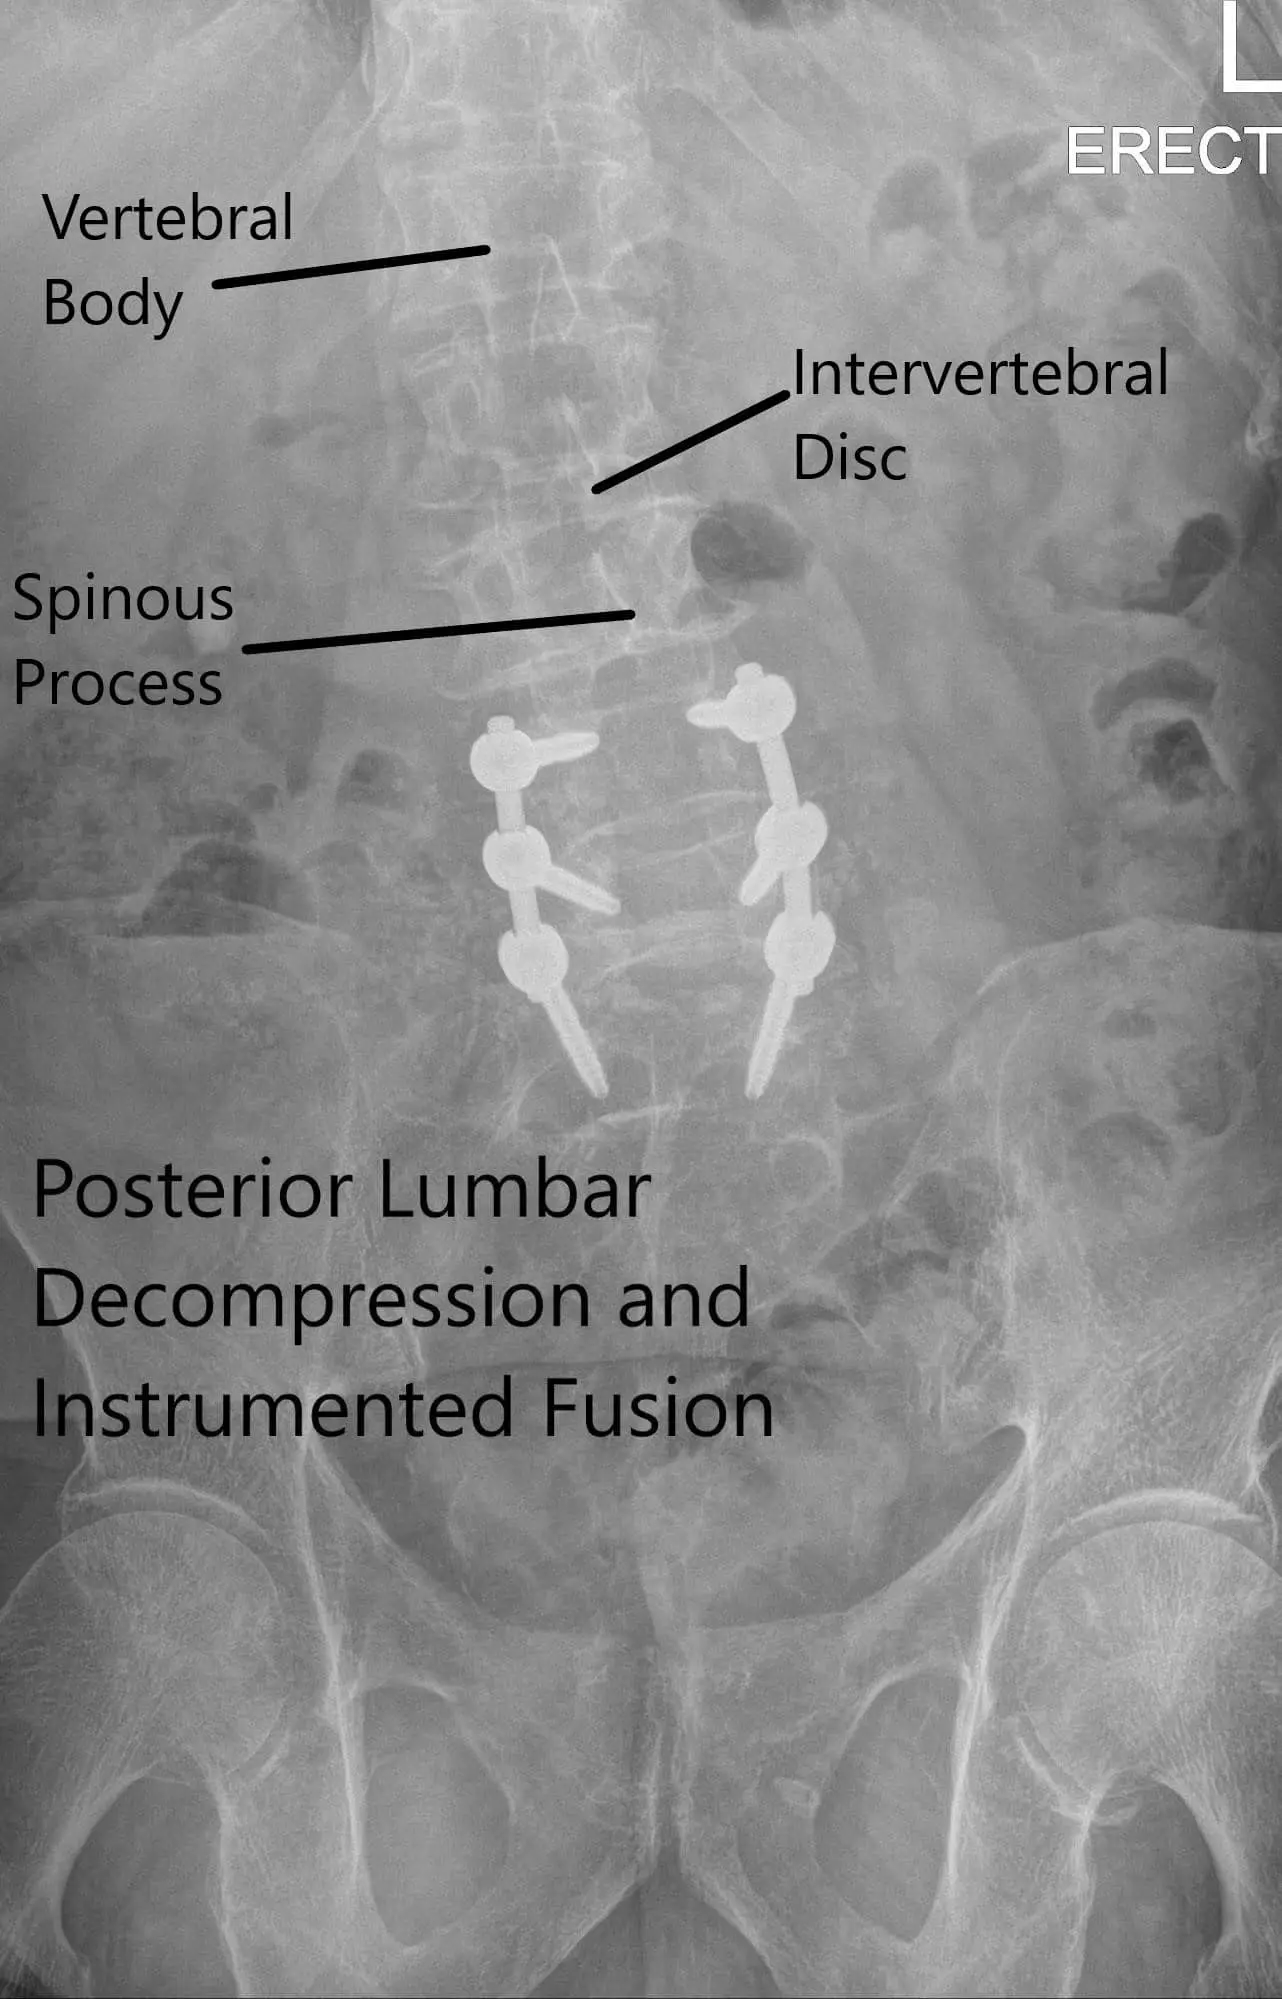

Postoperative X-ray showing AP and Lateral Views.

The patient agreed with the plan of Decomp L3-S1, separation surgery, Pedicle screw fixation, and posterolateral fusion L4-S1 using local autograft and cancellous chips and bone allograft.

The screws were lined and rods were placed on both sides and tightened to the screw heads. The final pictures of the screw were taken with C-arm and saved. Hemostasis was achieved. Vancomycin antibiotic was sprinkled into the wound. Considering the durotomy a deep suction drain was not put. The closure was done in layers. Two suprafascial drains were put. The counts were completed, checked, and correct at the end of the procedure. The patient was transferred into a supine position on the bed, extubated, and moved to the postoperative care unit in a stable condition.